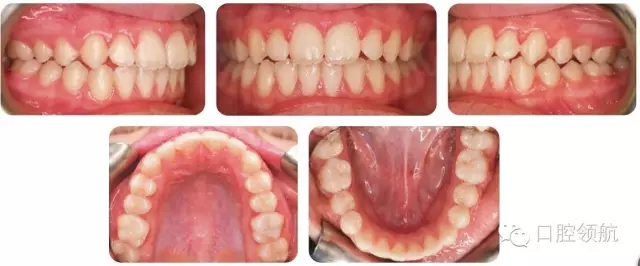

考慮拔牙牙位時,一般會選擇多生牙;但也要仔細(xì)評估正常牙和多生牙的冠根解剖,再決定拔牙牙位。這個病例中,更靠遠(yuǎn)中的側(cè)切牙(多生牙)被拔除。圖2.2是經(jīng)過功能矯治和固定矯治后的最終口內(nèi)像。

圖2.2